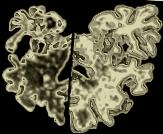

Actualmente, cada año se registran unos seis nuevos casos de este mal degenerativo en Massachusetts, los cuales casi siempre terminan en una muerte rápida tras el deterioro de las facultades mentales y físicas. En el examen post mórtem se evidencian las lesiones cerebrales, que convierten en algo similar a una esponja a los tejidos.